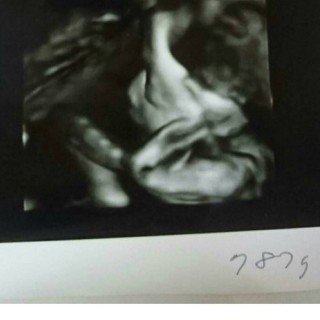

787gの女の子確定でした。 やっと顔を見せてくれました。 パパいわく、鼻はパパ、口はママだそうです。(笑) エコー中も足で蹴って元気でした。 手の腕枕が可愛い。 次は2週間後なので、楽しみです。